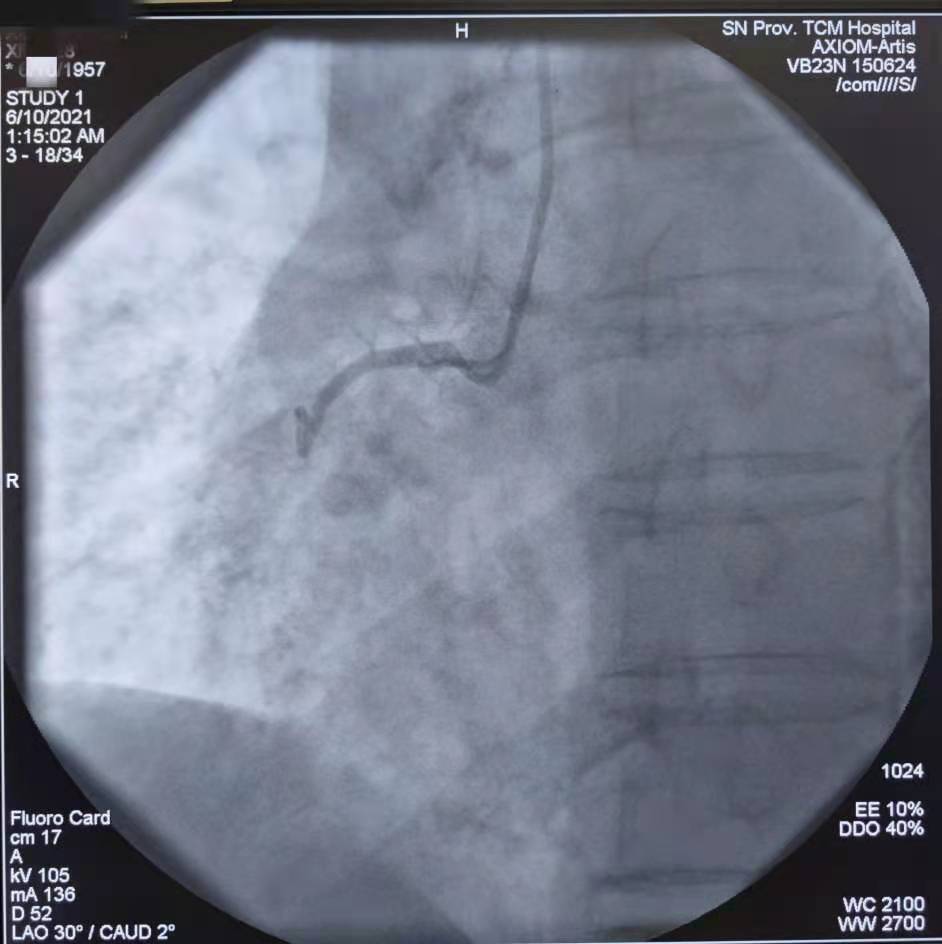

PCI术前